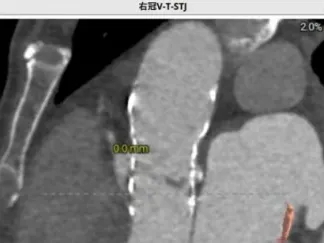

冠脉风险评估

术前讨论:患者77岁老年男性,3年前行TAVR术,此次再发主动脉瓣关闭不全,经评估排除感染,考虑主动脉瓣生物瓣毁损,患者心衰重,消瘦、虚弱,经多学科讨论,TAVR in TAVR手术指征明确,考虑行TAVR in TAVR治疗,术前评估瓣架内径:瓣环26.6,LVOT 26.6,瓣架位于瓣环以下:5(无窦)-13(左窦)mm,左侧冠脉高度12.1,右侧13.4,左冠VTC5.3mm VT-STJ:0mm,右冠VTC4.4mm VT-STJ0mm, 主动脉弓部角度可,存在钙化,双侧髂股动脉内径可,右侧股动脉分叉位于股骨头平面中部 左侧股动脉分叉位于股骨头下缘中部,建议左侧入路,拟植入29号瓣膜,因患者冠脉风险大,需控制瓣膜植入深度,拟控制S3上缘位于启明第3-4个交接点处,同时需关注冠脉(Guidzilla预置保护)。